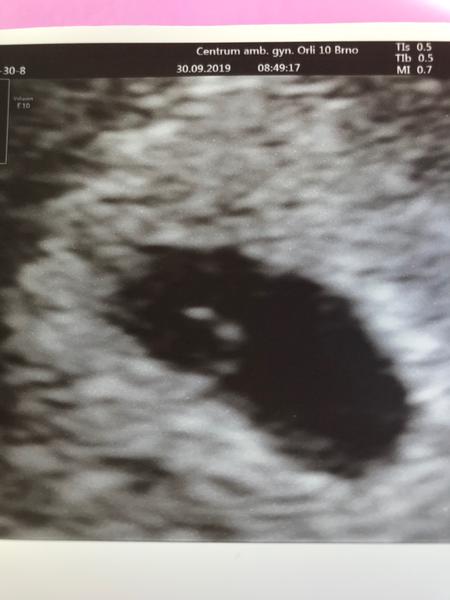

@maminka2020 Tak já měla dva týdny zpět úplně stejný obrázek (prázdný gestační váček - 5. týden). Objednali mě moc brzy a dva týdny jsem se zbytečně stresovala. Min. týden jsem byla na kontrolním ultrazvuku a bylo tam krásně vidět i srdíčko. Prostě jsem měla ovulaci později. Držím pěsti, ať to dobře dopadne.

@maminka2020 Mám z 6+2